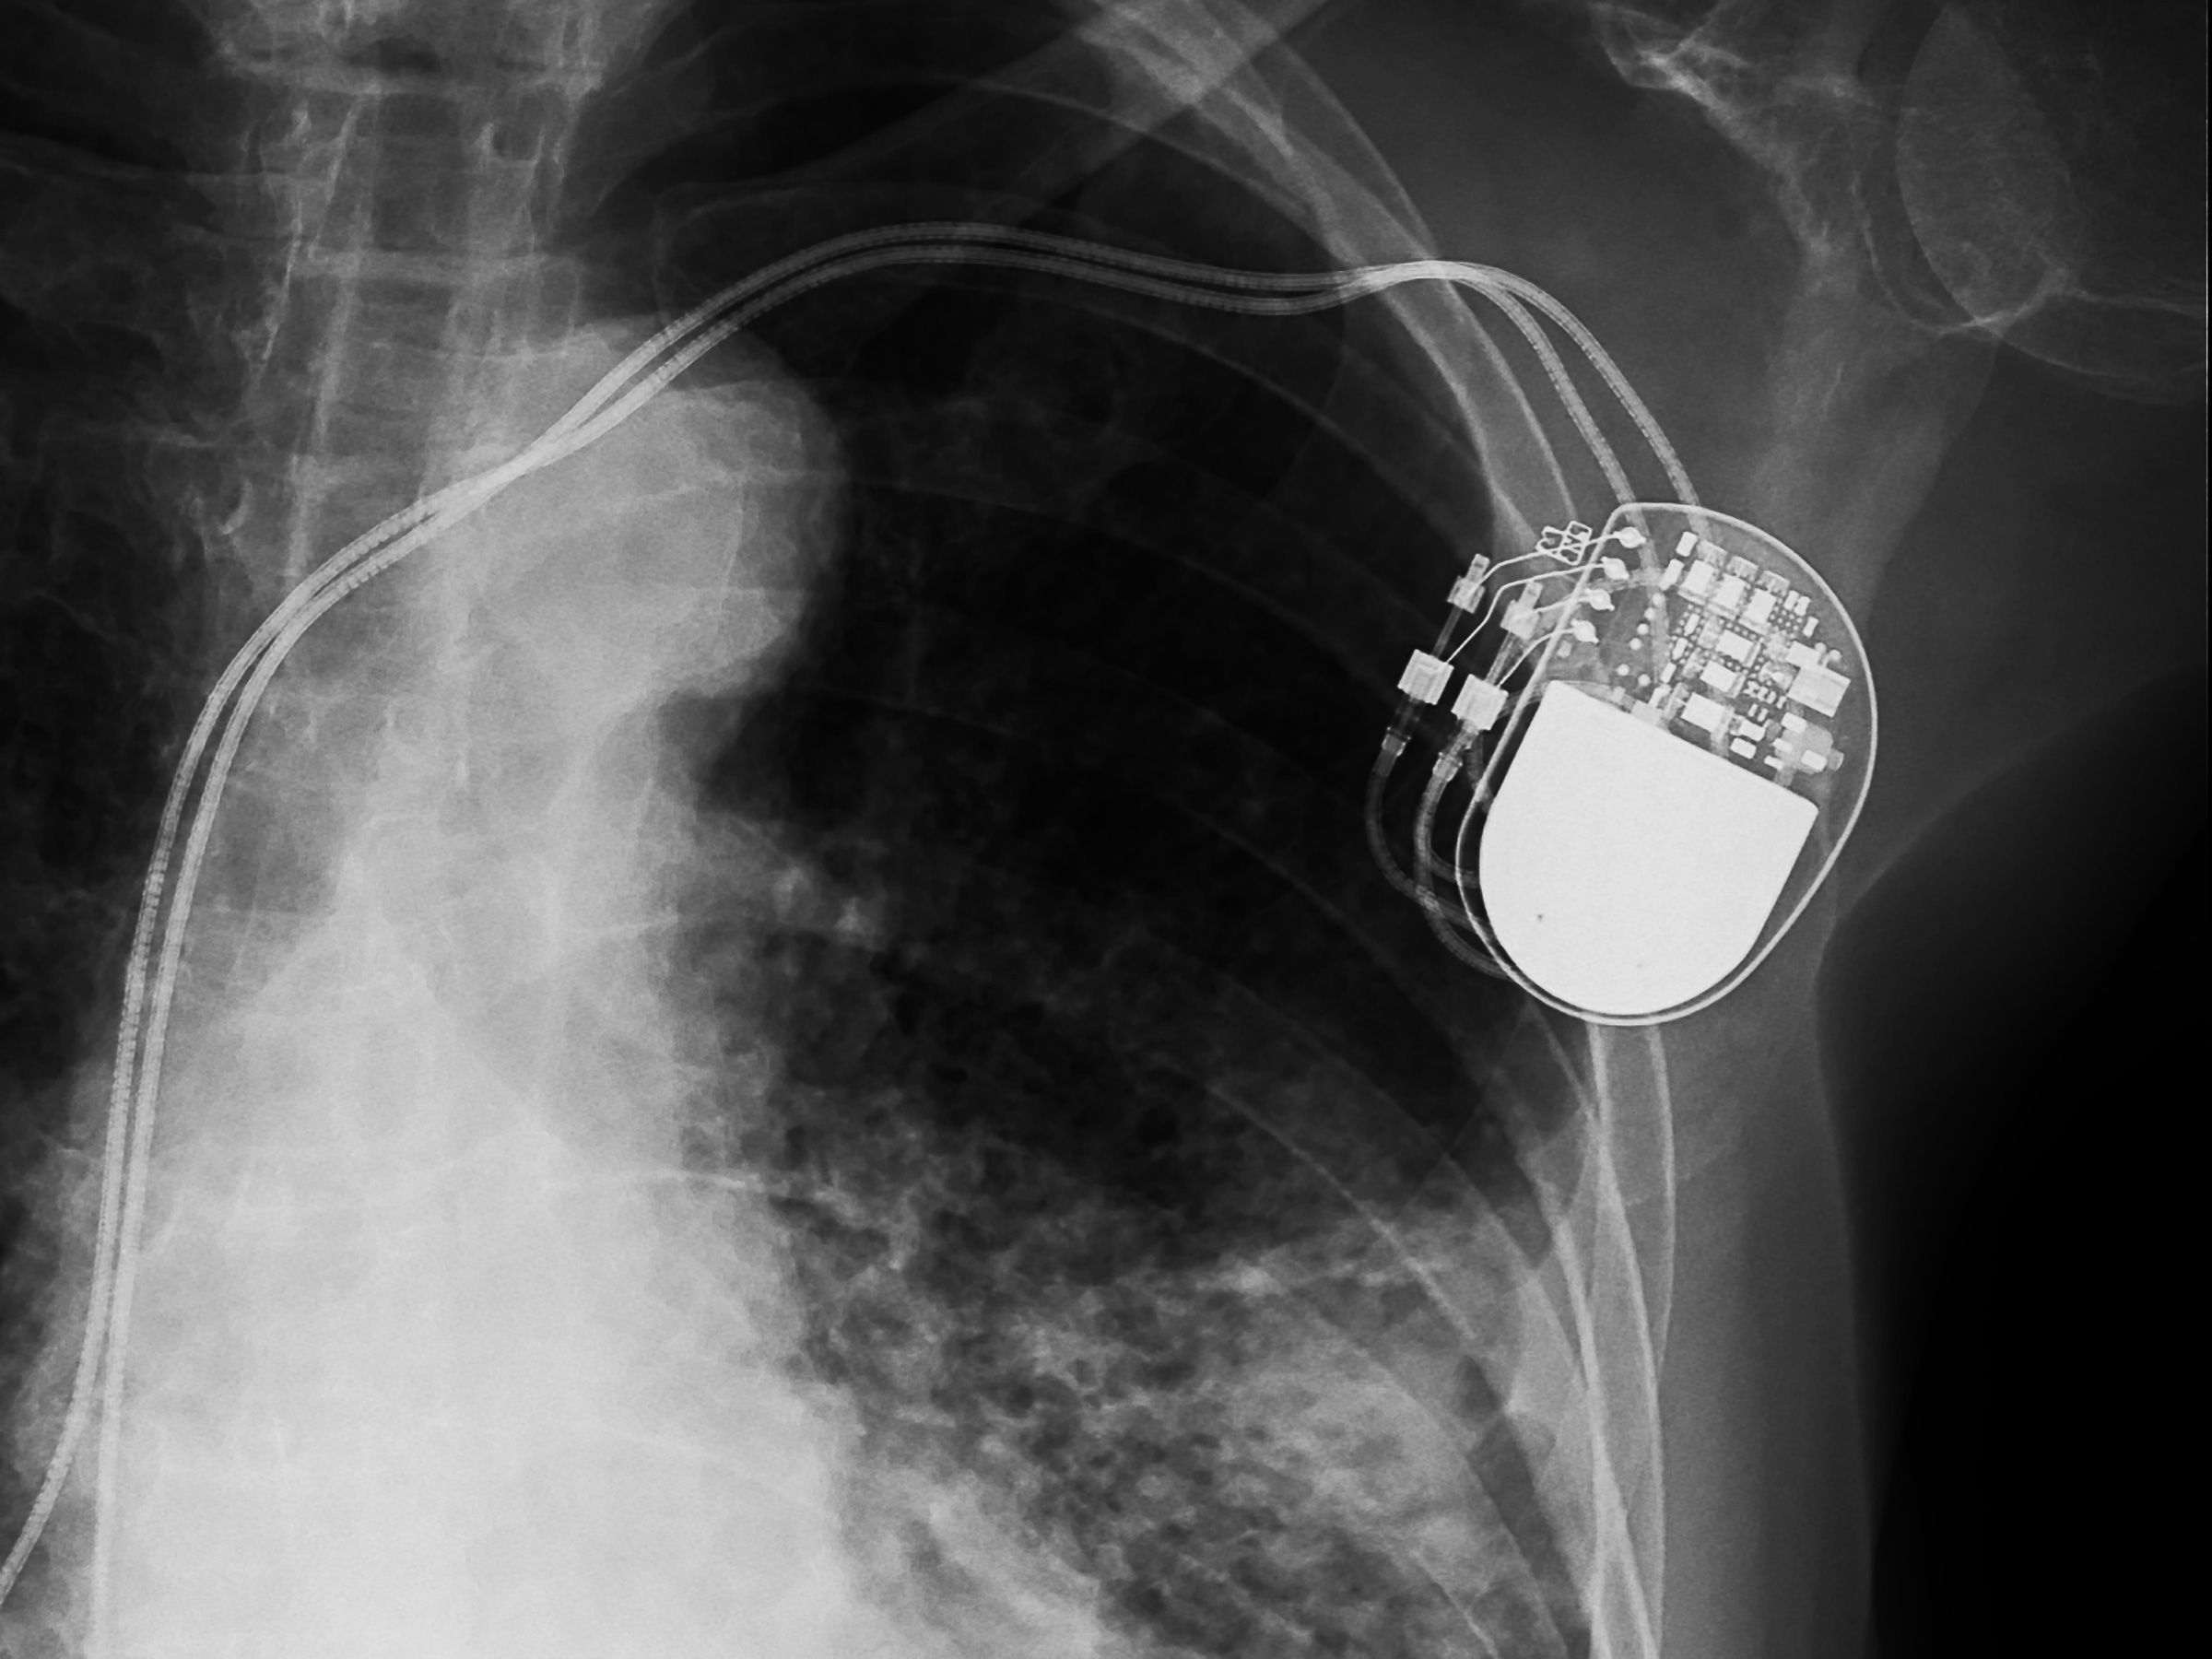

In 2018, Medtronic Plc found vulnerabilities in one of its pacemakers that, if exploited, "could result in harm to a patient depending on the extent and intent of a malicious cyberattack." The medical device maker disabled internet updates for ~34,000 devices in response. The following year, Medtronic discovered another cybersecurity issue when the FDA issued a recall for two insulin pumps upon discovering they could be remotely accessed and programmed to administer unsafe doses of insulin to its user.